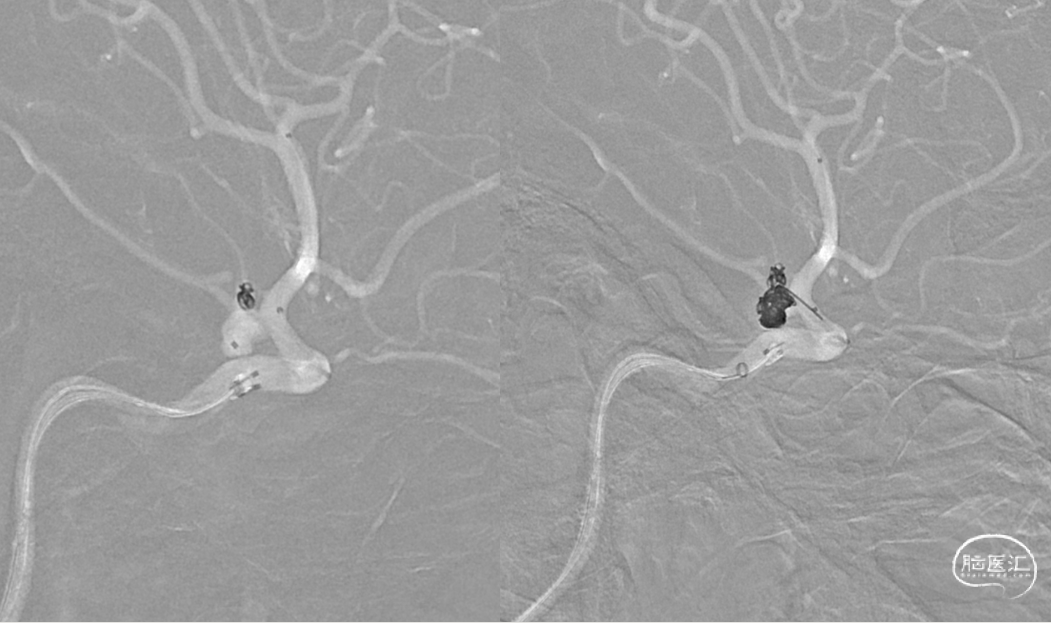

在Synchro0.014 200mm微导丝携带下将Excrlsior SL-10微导管置于左侧大脑中动脉M1远端,在Synchro-0.014 200cm微导丝携带下将两根Echelon-10微导管塑形后送至瘤腔内

分别将1.5mm*4cm弹簧圈送入子瘤,主瘤体送入6mm*20cm,5mm*15cm,1.5mm*4cm弹簧圈(EV3),沿SL-10微导管将4mmx21mm支架(Neuroform Atlas)置入左侧颈内动脉至左侧大脑中动脉

复查造影动脉瘤少量充盈,继续将3枚1mm*3cm弹簧圈(EV3)沿子瘤的Echelon-10微导管送入。复查造影示左侧颈内动脉、左大脑中动脉、大脑前动脉、左侧后交通动脉显影良好,动脉瘤栓塞完全。